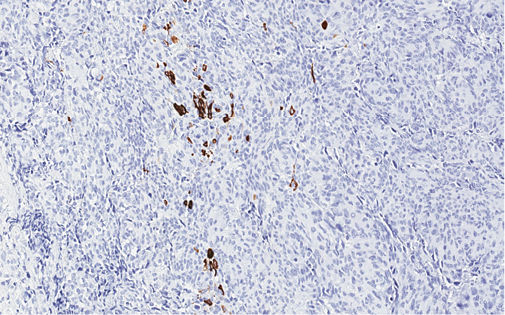

4 pav. Tik imunohistocheminiais metodais (MUC2) identifikuojama abortyvi mucinų produkcija pavienėse naviko ląstelėse

Imunohistocheminio profiliavimo metu nustatyta stipri difuzinė PanCK reakcija visuose komponentuose (3 pav.) ir menka, tačiau definityvi MUC2 žarninio tipo mucinų produkcija (4 pav.) kartu su tipiška KRAS geno 12-o kodono mutacija 2-ame egzone leistų klasifikuoti naviką kaip aukšto laipsnio (blogai diferencijuotą) adenokarcinomą. Ieškant biologinio pagrindo neįprastai naviko morfologijai paaiškinti atliktos papildomos imunohistocheminės reakcijos: Hep-Par1 (neigiama), INI1 (praradimo nėra), BRAF (neigiamas, tikėtina, nemutuotas), PMS2 ir MSH6 (reakcija išlikusi, nėra mikrosatelitų nestabilumo audinyje požymių), visose naviko ląstelių populiacijose patvirtintas jau biopsijoje identifikuotas difuzinis neuroendokrininis fenotipas (100 % Synaptophysin ir 95 % Chromogranin A ekspresija (5 pav.)). Ki67 proliferacinis aktyvumas buvo heterogeniškas ir rabdoidinės išvaizdos komponente siekė 90 proc., o likusiuose buvo perpus žemesnis (6 pav.).